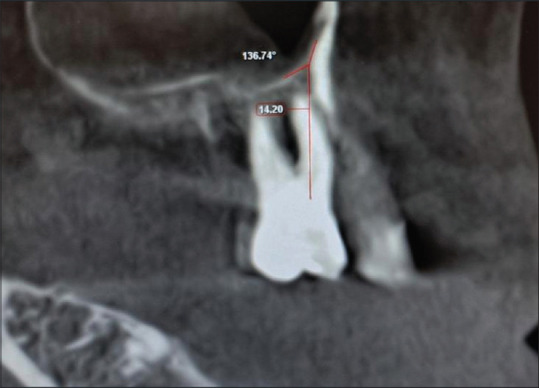

Background: Implant placement in the posterior maxilla is challenging in the case of maxillary sinus pneumatization. Increasing the vertical dimension by grafting the sinus floor is a common surgical modality. Cone-beam computed tomography (CBCT) scans are used to assess the presurgical anatomic variations of the maxillary sinus and determine the difficulty that might be encountered while performing sinus elevation. The sinus membrane is elevated from both the lateral and mesial walls of the sinus. The location and angulation of the palatal-nasal recess (PNR) on the medial wall of the sinus could complicate the elevation of the sinus membrane in this region. This study aimed to assess the angulation of the PNR and its position with respect to the alveolar crest in dentulous and edentulous subjects in the 1st molar region on CBCT scans.

Materials and methods: One hundred and fifty-two scans were selected from the department database. Sagittal sections including the 1st molar region were selected and measurements made. The PNR height was measured from the alveolar crest in millimeters and angulation in degrees and compared between the dentulous and edentulous groups.

Results: The dentulous group showed a statistically significant greater distance (10.4 ± 2.8 mm) between the alveolar crest and PNR as compared to the edentulous group (8.08 ± 3.1 mm). The edentulous group showed a statistically significant greater PNR angle (139.6o ± 13.6o) as compared to the dentulous group (133.4o ± 16.4o).